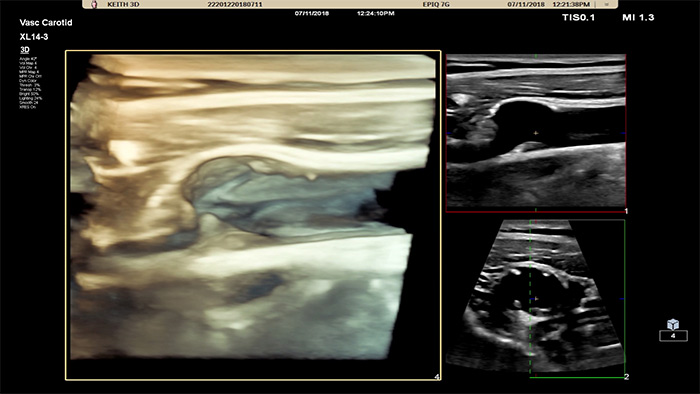

L’interface utilisateur 3D/4D permet également de générer un moulage du vaisseau en utilisant les flux de données. L’image du vaisseau 3D permet la visualisation directe du flux pour une analyse plus approfondie des états sténosés ou tortueux. Atout majeur : la visualisation 3D/4D de haute qualité de l’anatomie vasculaire constitue un outil de communication idéal pour faciliter la prise de décision clinique parmi les professionnels de la santé et améliorer la consultation avec les patients afin de les aider à comprendre leur état.